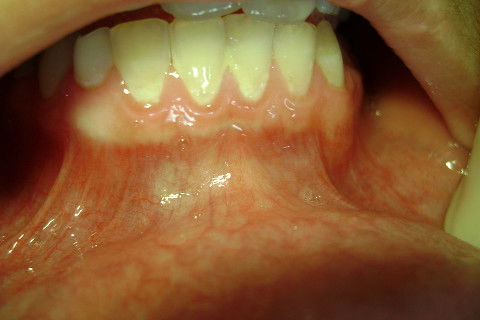

Aspecto inicial, foi preciso fazer uma profilaxia com jato de bicarbonato antes da cirurgia.